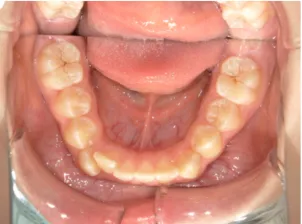

治療中➁小6:QH・BHでアーチ形態改善・上顎前歯を並べる

| 行ったご提案・診断内容 | 生え変わりが終わってなくマルチブラケット法による咬合治療には早い時期のため、顔立ちの成長を促す目的で歯列弓(アーチ)の拡大と前歯を並べながら永久歯が生えるのを待ち、咬合治療開始時に再診断で抜歯、非抜歯を最終検討する提案をしました。 再診断時(写真②)、歯列の拡大と上顎前歯の並べ替えはされていましたが八重歯となったため抜歯、非抜歯を検討しました。 口元は特に問題がなく非抜歯で八重歯を改善するためのスペースを作ることが可能なため非抜歯治療を提案しました。 治療は、 ・拡大および上顎左右6を遠心移動させてスペースを作る 予定装置 |